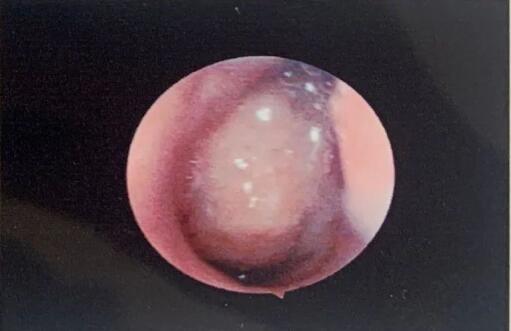

儿童耳鼻喉专家赵敏医生查体后,安排了耳鼻喉相关检查,鼻咽内镜查见:“双侧鼻腔粘膜慢性充血;鼻咽部见腺样体增生、肥大,堵塞后鼻孔,圆枕受压。”

(内镜检查报告)

赵敏医生通过内窥镜检查结合耳科相关检查诊断:“腺样体肥大、分泌性中耳炎”,考虑到患者腺样体已堵塞后鼻孔2/3,且引起了耳部症状,且已采取保守治疗,遂建议通过手术进行治疗。